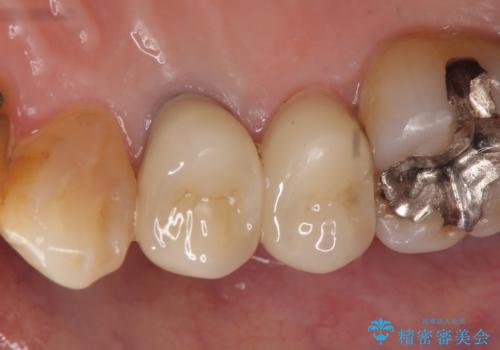

- 右上4番目の歯が黒くなっているのが気になるといらっしゃった方の症例です。

再根管治療後、オールセラミッククラウンによる補綴を行いました。

右上5も虫歯があったためオールセラミッククラウンによる補綴を行っております。